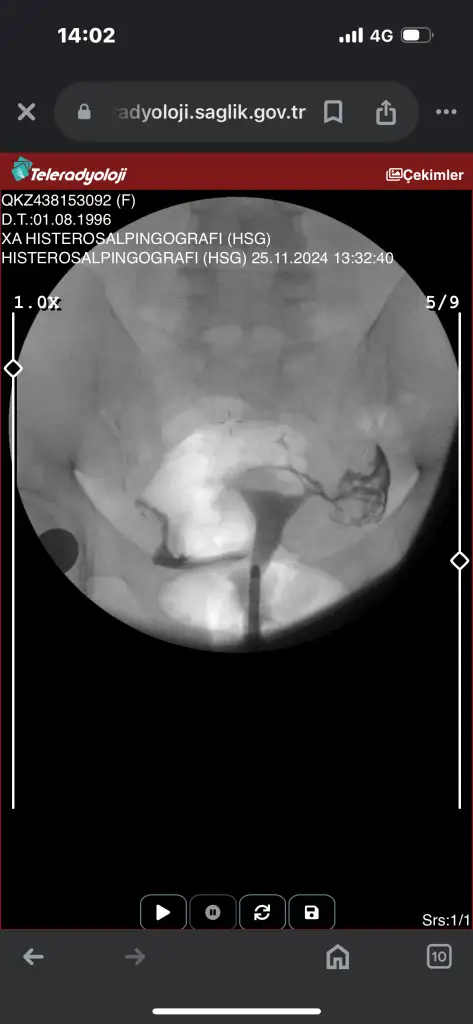

Canım tek tüpün kapalı galibaKızlar acil sonucuma bakarmısınızz ben hiçbirşey anlamıormm